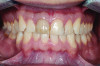

Figure 8. Final restorations, retracted view.

Figure 8